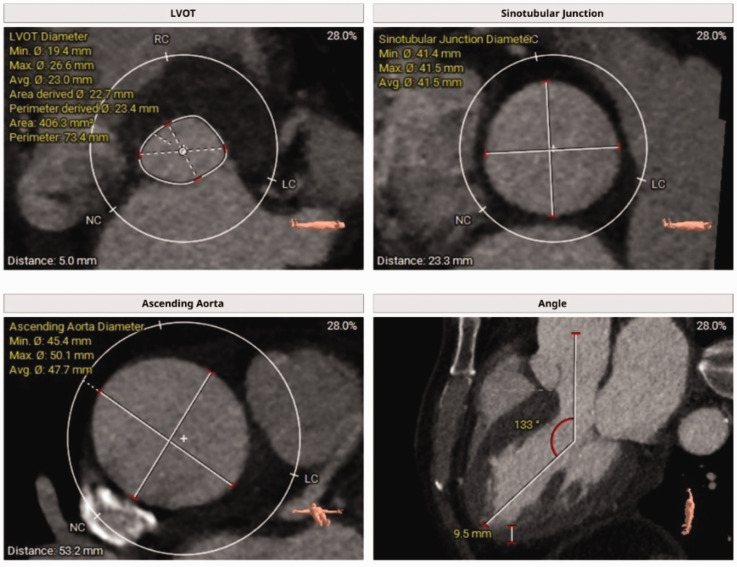

This case report details the successful use of JenaValve for transcatheter aortic valve implantation in a male patient in his early 50s with severe aortic regurgitation. The patient had multiple comorbidities, including chronic kidney disease and heart failure, increasing the risk of surgical intervention. JenaValve, a second-generation device with unique positioning and anchoring mechanisms, was deployed successfully, resulting in immediate improvements in cardiac function without significant regurgitation or paravalvular leakage. This case highlights the potential of transcatheter aortic valve implantation as a viable alternative to surgical aortic valve replacement in patients with severe aortic regurgitation, emphasizing the importance of technological advancements and a multidisciplinary approach in managing complex cardiovascular cases. Long-term follow-up is essential to assess the durability of the implanted valve and the patient's overall prognosis.